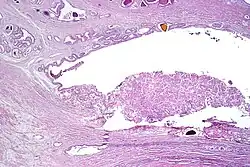

-

Intraductal carcinoma of the prostate with an infiltrative growth pattern may be morphologically difficult to distinguish from invasive cancer. One focus shows comedonecrosis (arrow), morphologically suggesting Gleason pattern 5 invasive carcinoma (a haematoxylin and eosin, b CK5/6)[20] -

Intraductal carcinoma of the prostate with very patchy basal cells identified by immunohistochemistry. At least some of the glands lacking basal cell immunoreactivity represent intraductal rather than invasive carcinoma (a haematoxylin and eosin, b CK 5/6)[20]